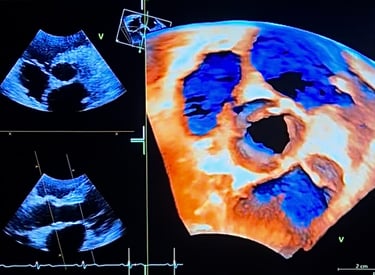

Echographie cardiaque (ETT)

Cette formation s’adresse à tous ceux qui souhaitent se former ou se perfectionner en échographie cardiaque. Qu’il s’agisse d’approfondir la 4D, la quantification des insuffisances valvulaires ou encore l’analyse des cardiomyopathies. Conçue sur mesure, elle accompagne aussi bien les professionnels en formation (DIU/DU d’échographie cardiovasculaire non invasive) que les praticiens déjà expérimentés. Vous y trouverez de nombreux cas cliniques concrets, des explications claires et des outils pratiques.